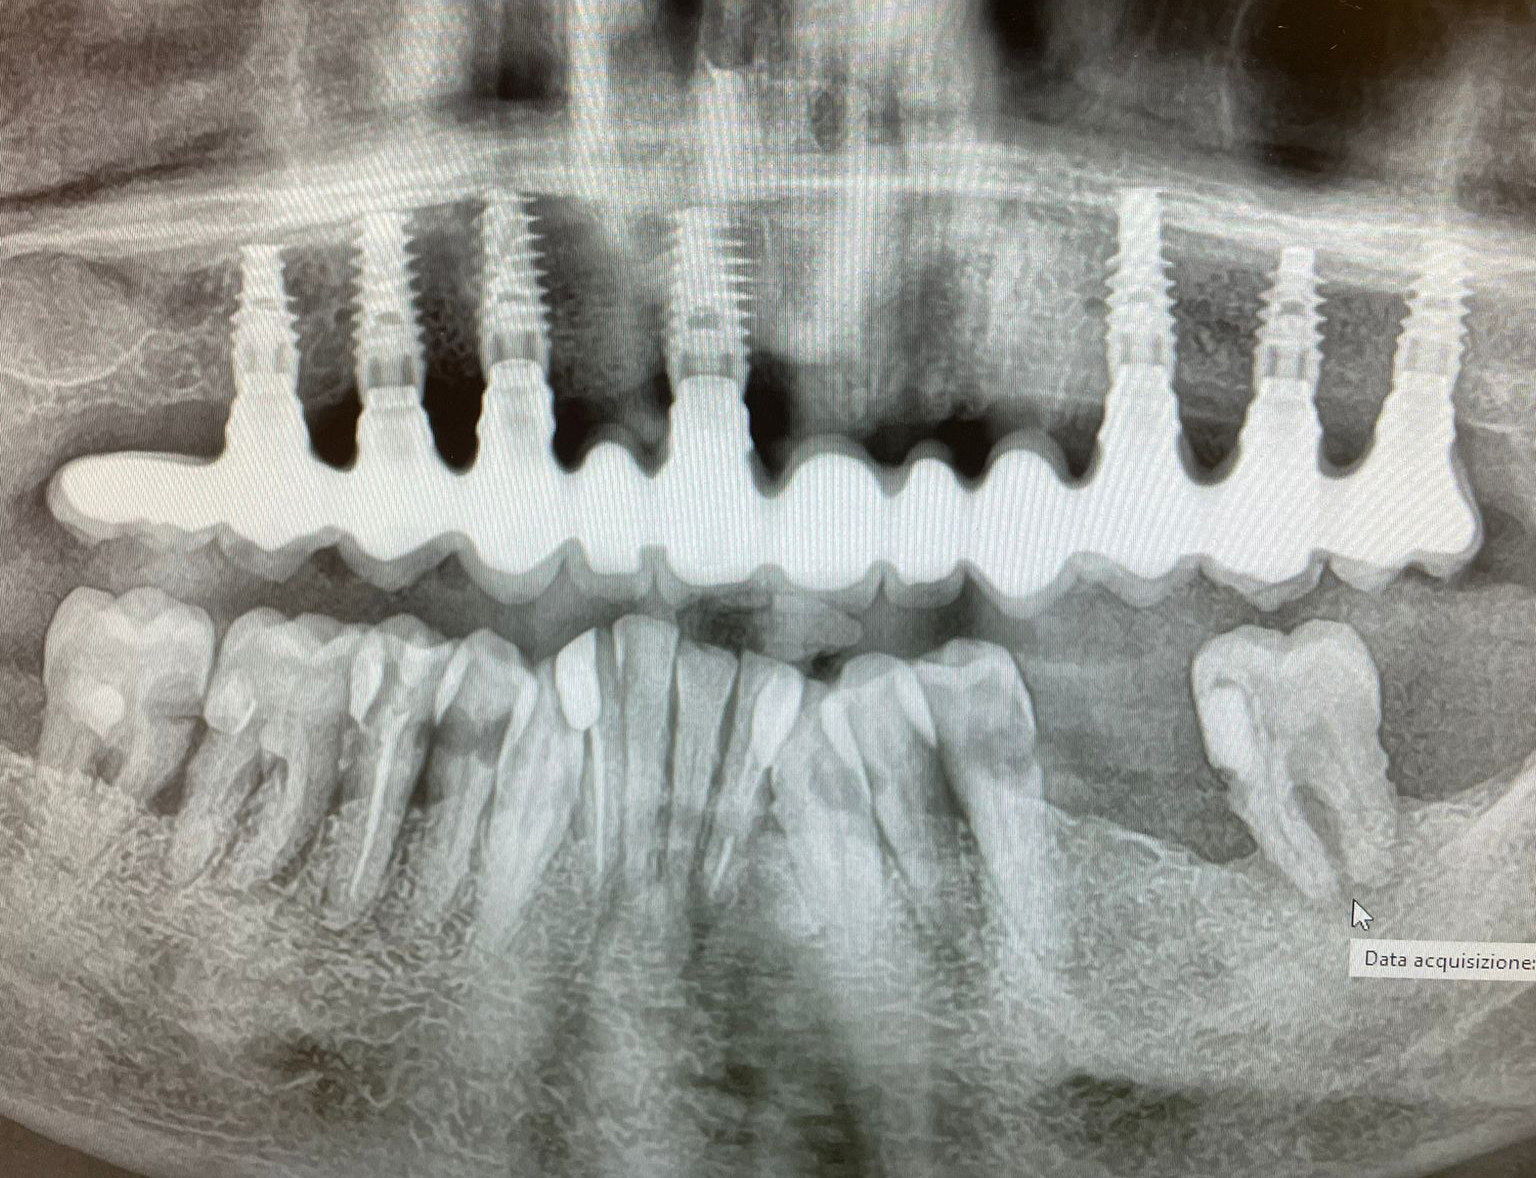

La consegna dall'arcata definitivamente ceramizzata e con le connessioni, solo minimamente pulite dall'ossido creato dai passaggi in forno, ha generato le radiografie di validazione della corretta lavorazione, sia meccanica che estetica, permettendo al paziente di tornare alla sua frizzante vita pubblica, sfoggiando un sorriso all'altezza dello studio Imburgia di Palermo (Fig. 22, 23).

Fig. 23. Radiografia panoramica di validazione e controllo dei corretti accoppiamenti implantoprotesici